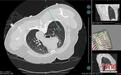

图为机器人引导下实际穿刺路径。广西医科大学第一附属医院 供图

当天,该院心胸外科主任阳诺带领消融团队开展手术。他介绍,在术前,穿刺手术机器人系统基于患者CT影像,能自动构建详细的肺部3D立体模型,清晰呈现结节与周围血管、气管等重要组织的位置关系。

“它就像一位‘智能导航员’,精准规划穿刺路径、角度与深度,有效避开血管、气管等重要组织结构,将误差控制在毫米级。”阳诺说。

术中,机器人就像有了“智慧眼睛”和“稳定双手”,整个过程机械臂平稳导航,无需调针,实现对靶病灶的“一针到位”,减少了CT扫描次数和患者的辐射暴露。机器人的应用避免了人为因素可能带来的穿刺偏差,从而减少对周围正常组织的损伤,降低了气胸、出血等并发症的发生率,也缩短了手术时间。